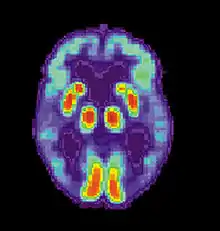

Neural systems used by procedural memory are commonly targeted by Human Immunodeficiency Virus; the striatum being the structure most notably affected.[64] MRI studies have even shown white matter irregularity and basal ganglia subcortical atrophy in these vital areas necessary for both procedural memory and motor-skill.[65] Applied research using various procedural memory tasks such as the Rotary pursuit, Mirror star tracing and Weather prediction tasks have shown that HIV positive individuals perform worse than HIV negative participants suggesting that poorer overall performance on tasks is due to the specific changes in the brain caused by the disease.[66]

Huntington's disease